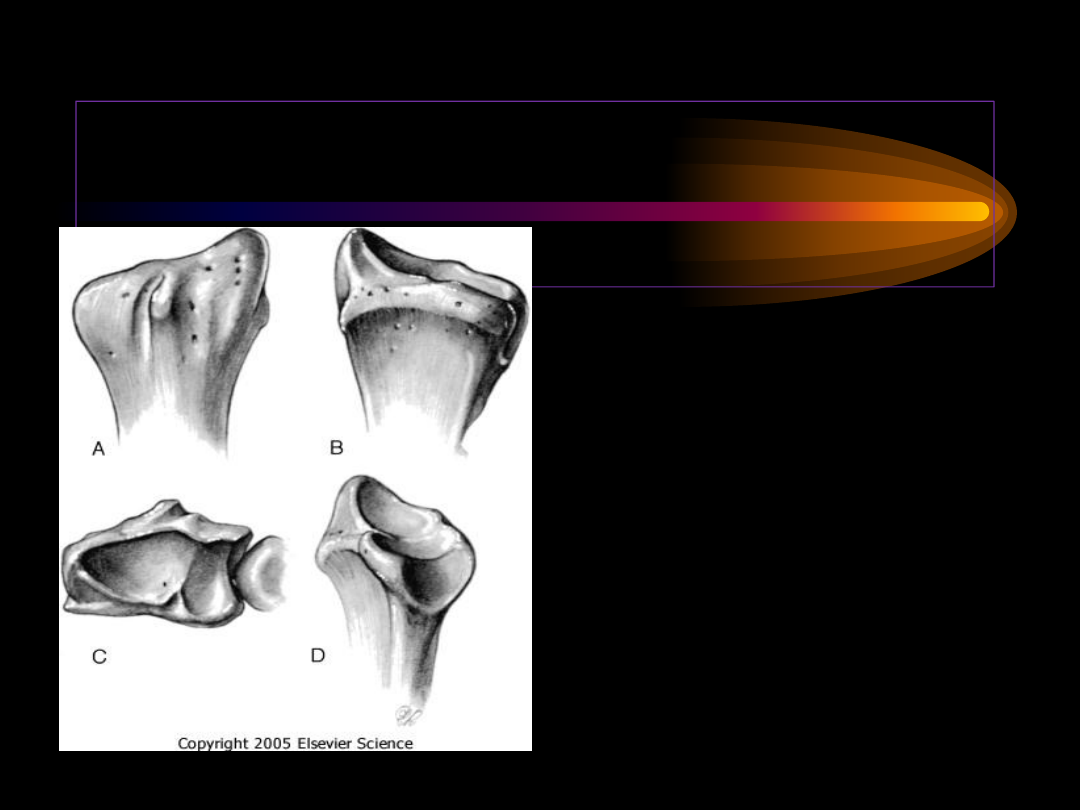

解剖

A,

Dorsal view illustrating Lister's

tubercle.

B,

Palmar view showing the

scaphoid  and  lunate fossae distally,

as well as the sigmoid  notch ulnarly.

Vascular  foramina can be noted on

the  palmar and dorsal aspects of the

distal radius.

C,

An end-on view of

the distal radius and radioulnar joint

showing  the  scaphoid fossa, lunate

fossa, and ulnar head resting in  the

sigmoid  notch.

D,

A  view  of  the

sigmoid notch from the ulnar aspect.